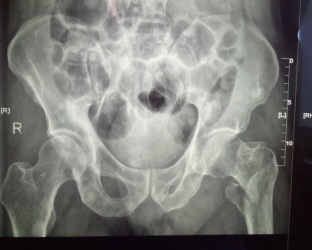

患者張XX,男,75歲,6月前腦梗塞遺留左側(cè)肢體偏癱,合并高血壓、糖尿病。

患者王XX,男80歲,前列腺癌骨轉(zhuǎn)移導(dǎo)致病理性骨折,合并房顫、高血壓、冠心病。

患者馬X,男,87歲,合并糖尿病、腦梗塞。